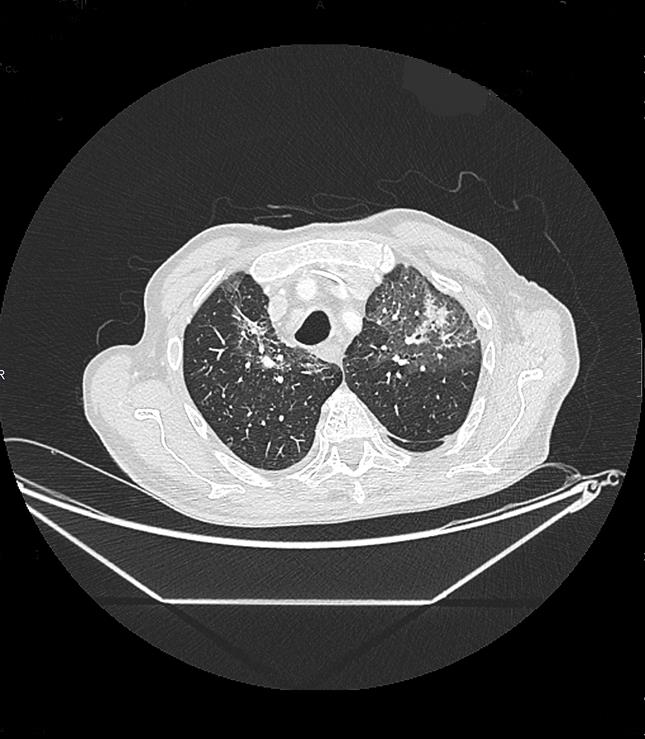

Como prueba complementaria realizaremos TC del tórax porque nos permite examinar anomalías encontradas en rx de tórax, ayuda a diagnosticar las causas de signos o síntomas clínicos de enfermedades de tórax (en este caso, fiebre) y evalúa las posibles lesiones en el tórax, incluyendo el corazón, los vasos sanguíneos, los pulmones, las costillas y la columna vertebral.

Haz click en las imágenes para verlas ampliadas